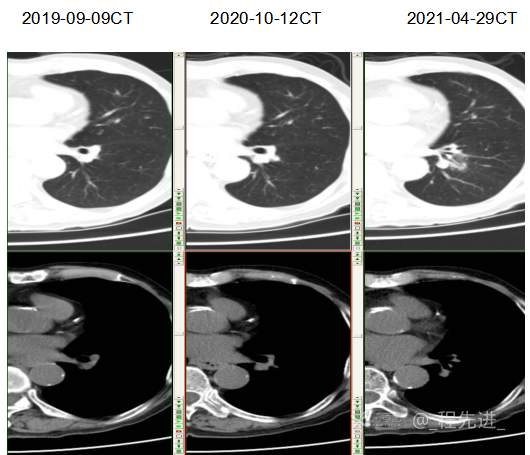

主诉: 反复咳嗽、咳痰10余年,加重10余天

现病史:患者10年前开始出现反复咳嗽、咳痰,3年前出现活动性气喘,休息后症状可缓解;冬春季节或受凉后症状加重,不伴反复下肢浮肿,曾在我院住院诊断为”慢性阻塞性肺疾病”,给予解痉平喘、化痰、输氧治疗有效,平素生活能自理,不能从事体力劳作,此次发病于10天前可能受凉后咳嗽、咳痰加重,咳黄痰,呈阵咳,咳白痰,活动气喘加重,不伴畏寒、发热,无胸痛,今来我院就诊,拟“慢性阻塞性肺病伴急性加重”收住入院,自发病以来,患者精神、食纳、睡眠一般,大小便如常,体重有下降,县体不详。患者及陪护人员:否认14天内离开过南丰,否认14天内有新型冠状病毒感染病例报告社区或中高风险地区的旅行史或居住史,否认14天内与新型冠状病毒感染的患者或无症状感染者有接触史,否认14天内曾接触过来自有病例报告社区或中高风险地区的发热或有呼吸道症状的患者,否认14天内在小范围如家庭、办公室、学校班级等场所,出现5例及以上发热和/或呼吸道症状的聚集性发病病例。